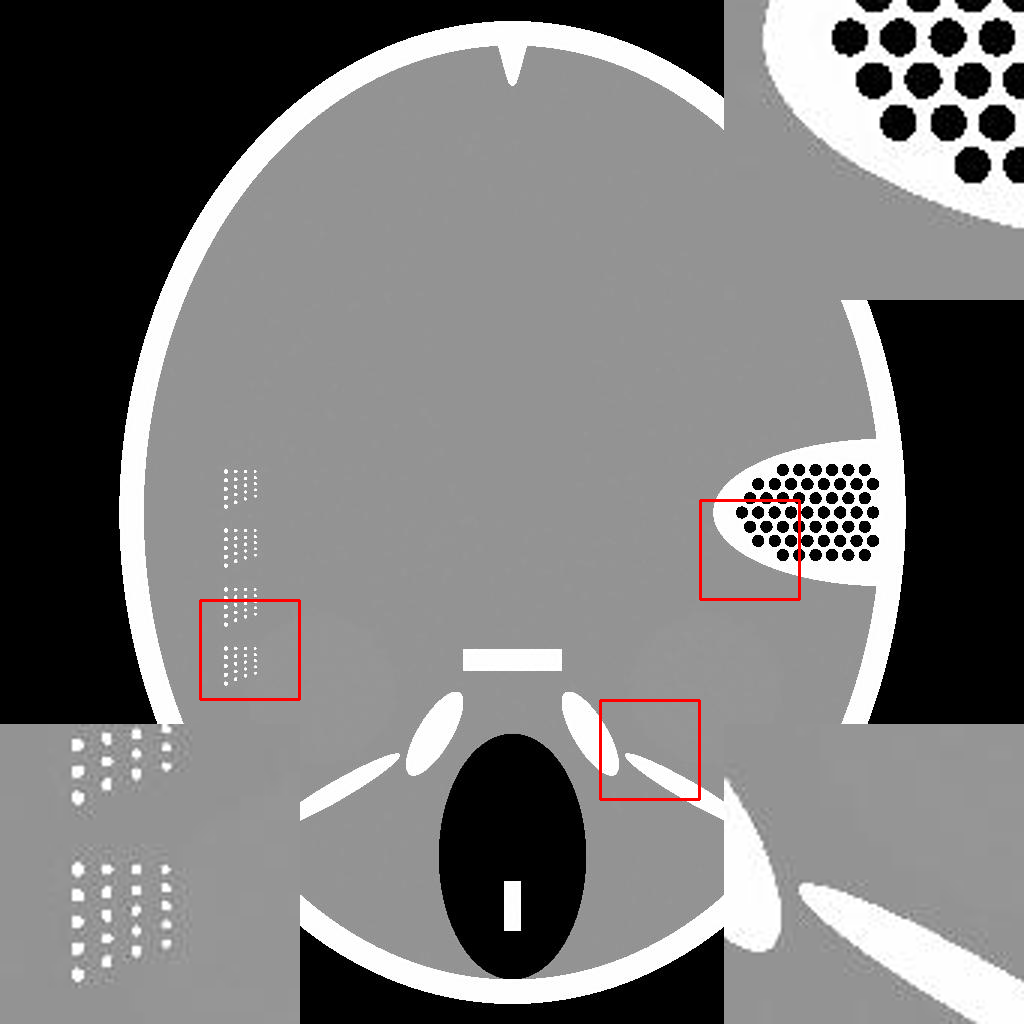

IV-E1 Rotation

The few-view CT reconstruction experiment is replicated, utilizing an identical test image rotated by degrees to simulate a rudimentary pose alteration of the patient. The reconstruction performances are shown in Fig.9, and the reconstruction results corresponding to views are shown in Fig.10. A similar experiment is also conducted under the limited-angle condition, yielding similar results.

V-C Non-Ideal Factors

In practical applications, the imaged object might exhibit inconsistencies with the training dataset due to various non-ideal factors. The rotation operation in Section IV-E serves as a simplified simulation of such discrepancies, which may arise from differing poses of patients. The impact on reconstruction accuracy is shown in Fig.9. The comparison between Fig.5b and Fig.9 reveals that the pre-trained MED50 method is predominantly affected by a considerable decline in SNR. The reconstruction results are also presented in Fig.10. In contrast to the first row of Fig.7, the MED50 reconstruction result lacks a completely black background and exhibits horizontal artifacts in the non-empty region. This observation suggests that MED50 cannot effectively handle the perturbations in the inference data. A similar result is also obtained when adding quantum noise to the sinogram.